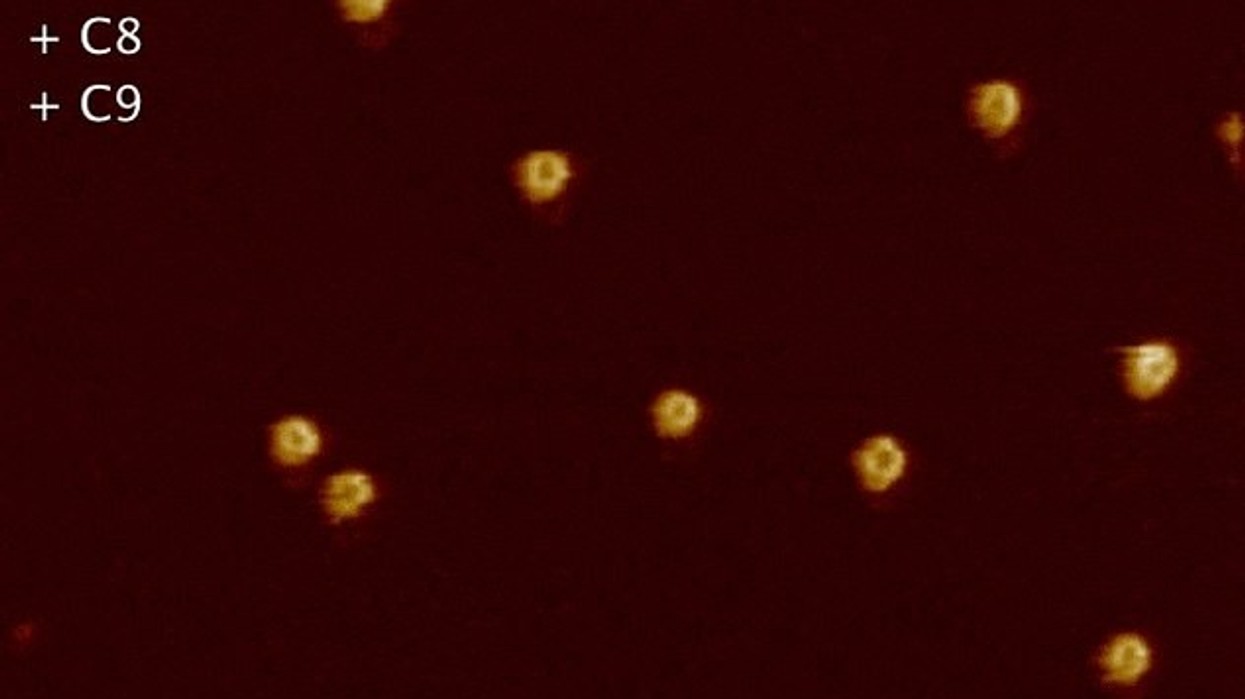

Vrimat kanë diametër prej vetëm dhjetë nanometrave - dhjetë mijë herë më e vogël se gjërësia e fijes së flokut, transmeton Telegrafi.

“Mendohet se këto nanomekanizma sulmuese, e presin momentin e duhur dhe veprojnë” ka thënë Dr Parson. Me këtë rast, ai beson se mekanizmi i sistemit imunitar, llogaritë mirë nëse qelizat janë të dëmshme apo të shoqërueshme, para se të kryejë goditjet.

Kjo mendohet se i mundëson vet trupit, që të intervenojë dhe të kryejë mbrojtjen e domosdoshme, në mënyrë që qarkullimi të shkojë si duhet. Nëpërmjet pamjeve të regjistruara, shkencëtarët kanë gjetur se si kryhet procesi i eliminimit, për të mbrojtur qelizat e shëndosha.

Shkencëtarët shfrytëzuan një kamerë më të hollë se xhilpëra, që merr pamje nga disa pjesë të sekondës, për të dokumentuar procesin specifik. /Telegrafi/